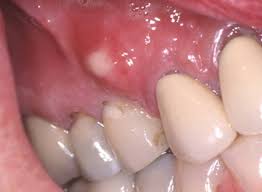

La fístula es la comunicación de la zona infectada en el hueso con el exterior y se suele manifestar como un puntito rojo o blanco en la encía.

La aparición de una fístula indica la existencia de infección en el hueso.

Fístula formada a partir de un absceso dentario apical, propagado a través del hueso alveolar hacia el seno maxilar, suelo bucal, bóveda palatina, vestíbulo oral o piel